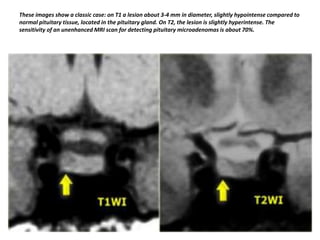

These images show a classic case: on T1 a lesion about 3-4 mm in diameter, slightly hypointense compared to

normal pituitary tissue, located in the pituitary gland. On T2, the lesion is slightly hyperintense. The

sensitivity of an unenhanced MRI scan for detecting pituitary microadenomas is about 70%.